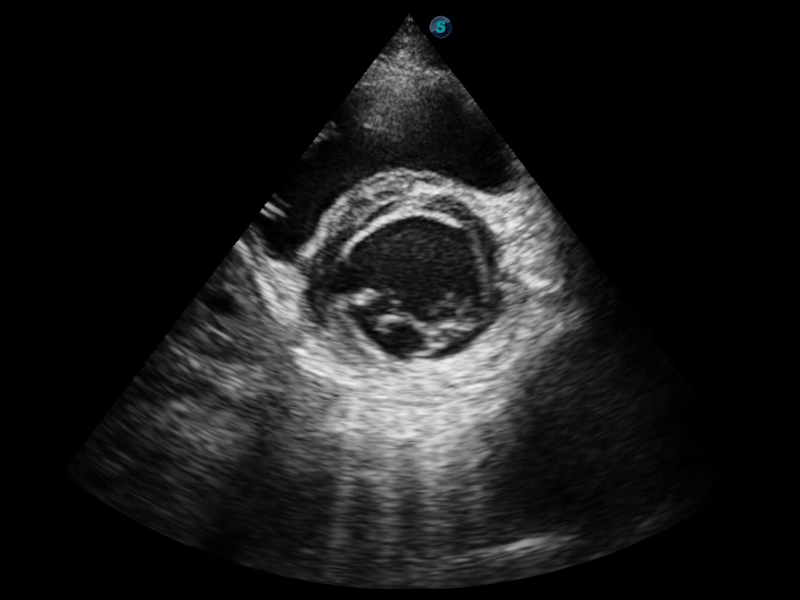

S-Live 高分辨率容积成像

通过仿真成像技术对3D/4D立体数据进行渲染,多种初始光源位置可选,并支持轨迹球360°光源位置自由调节,清晰显示不同方位容积图像细节。

临床图像